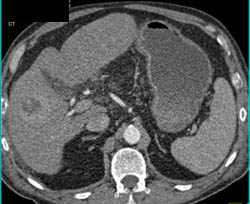

Portal Hypertension With Increased Flow Into Mesenteric Vessels